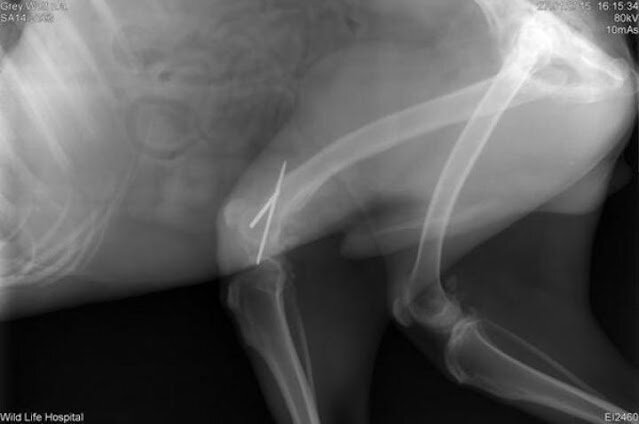

Zdjęcie rentgenowskie wyraźnie pokazało, że zwierzę ma złamaną tylną łapę.

Zaraz potem Oliel trafił na stół operacyjny, gdzie po narkozie założono mu gips. To był dopiero początek jego drogi do odzyskania zdrowia.